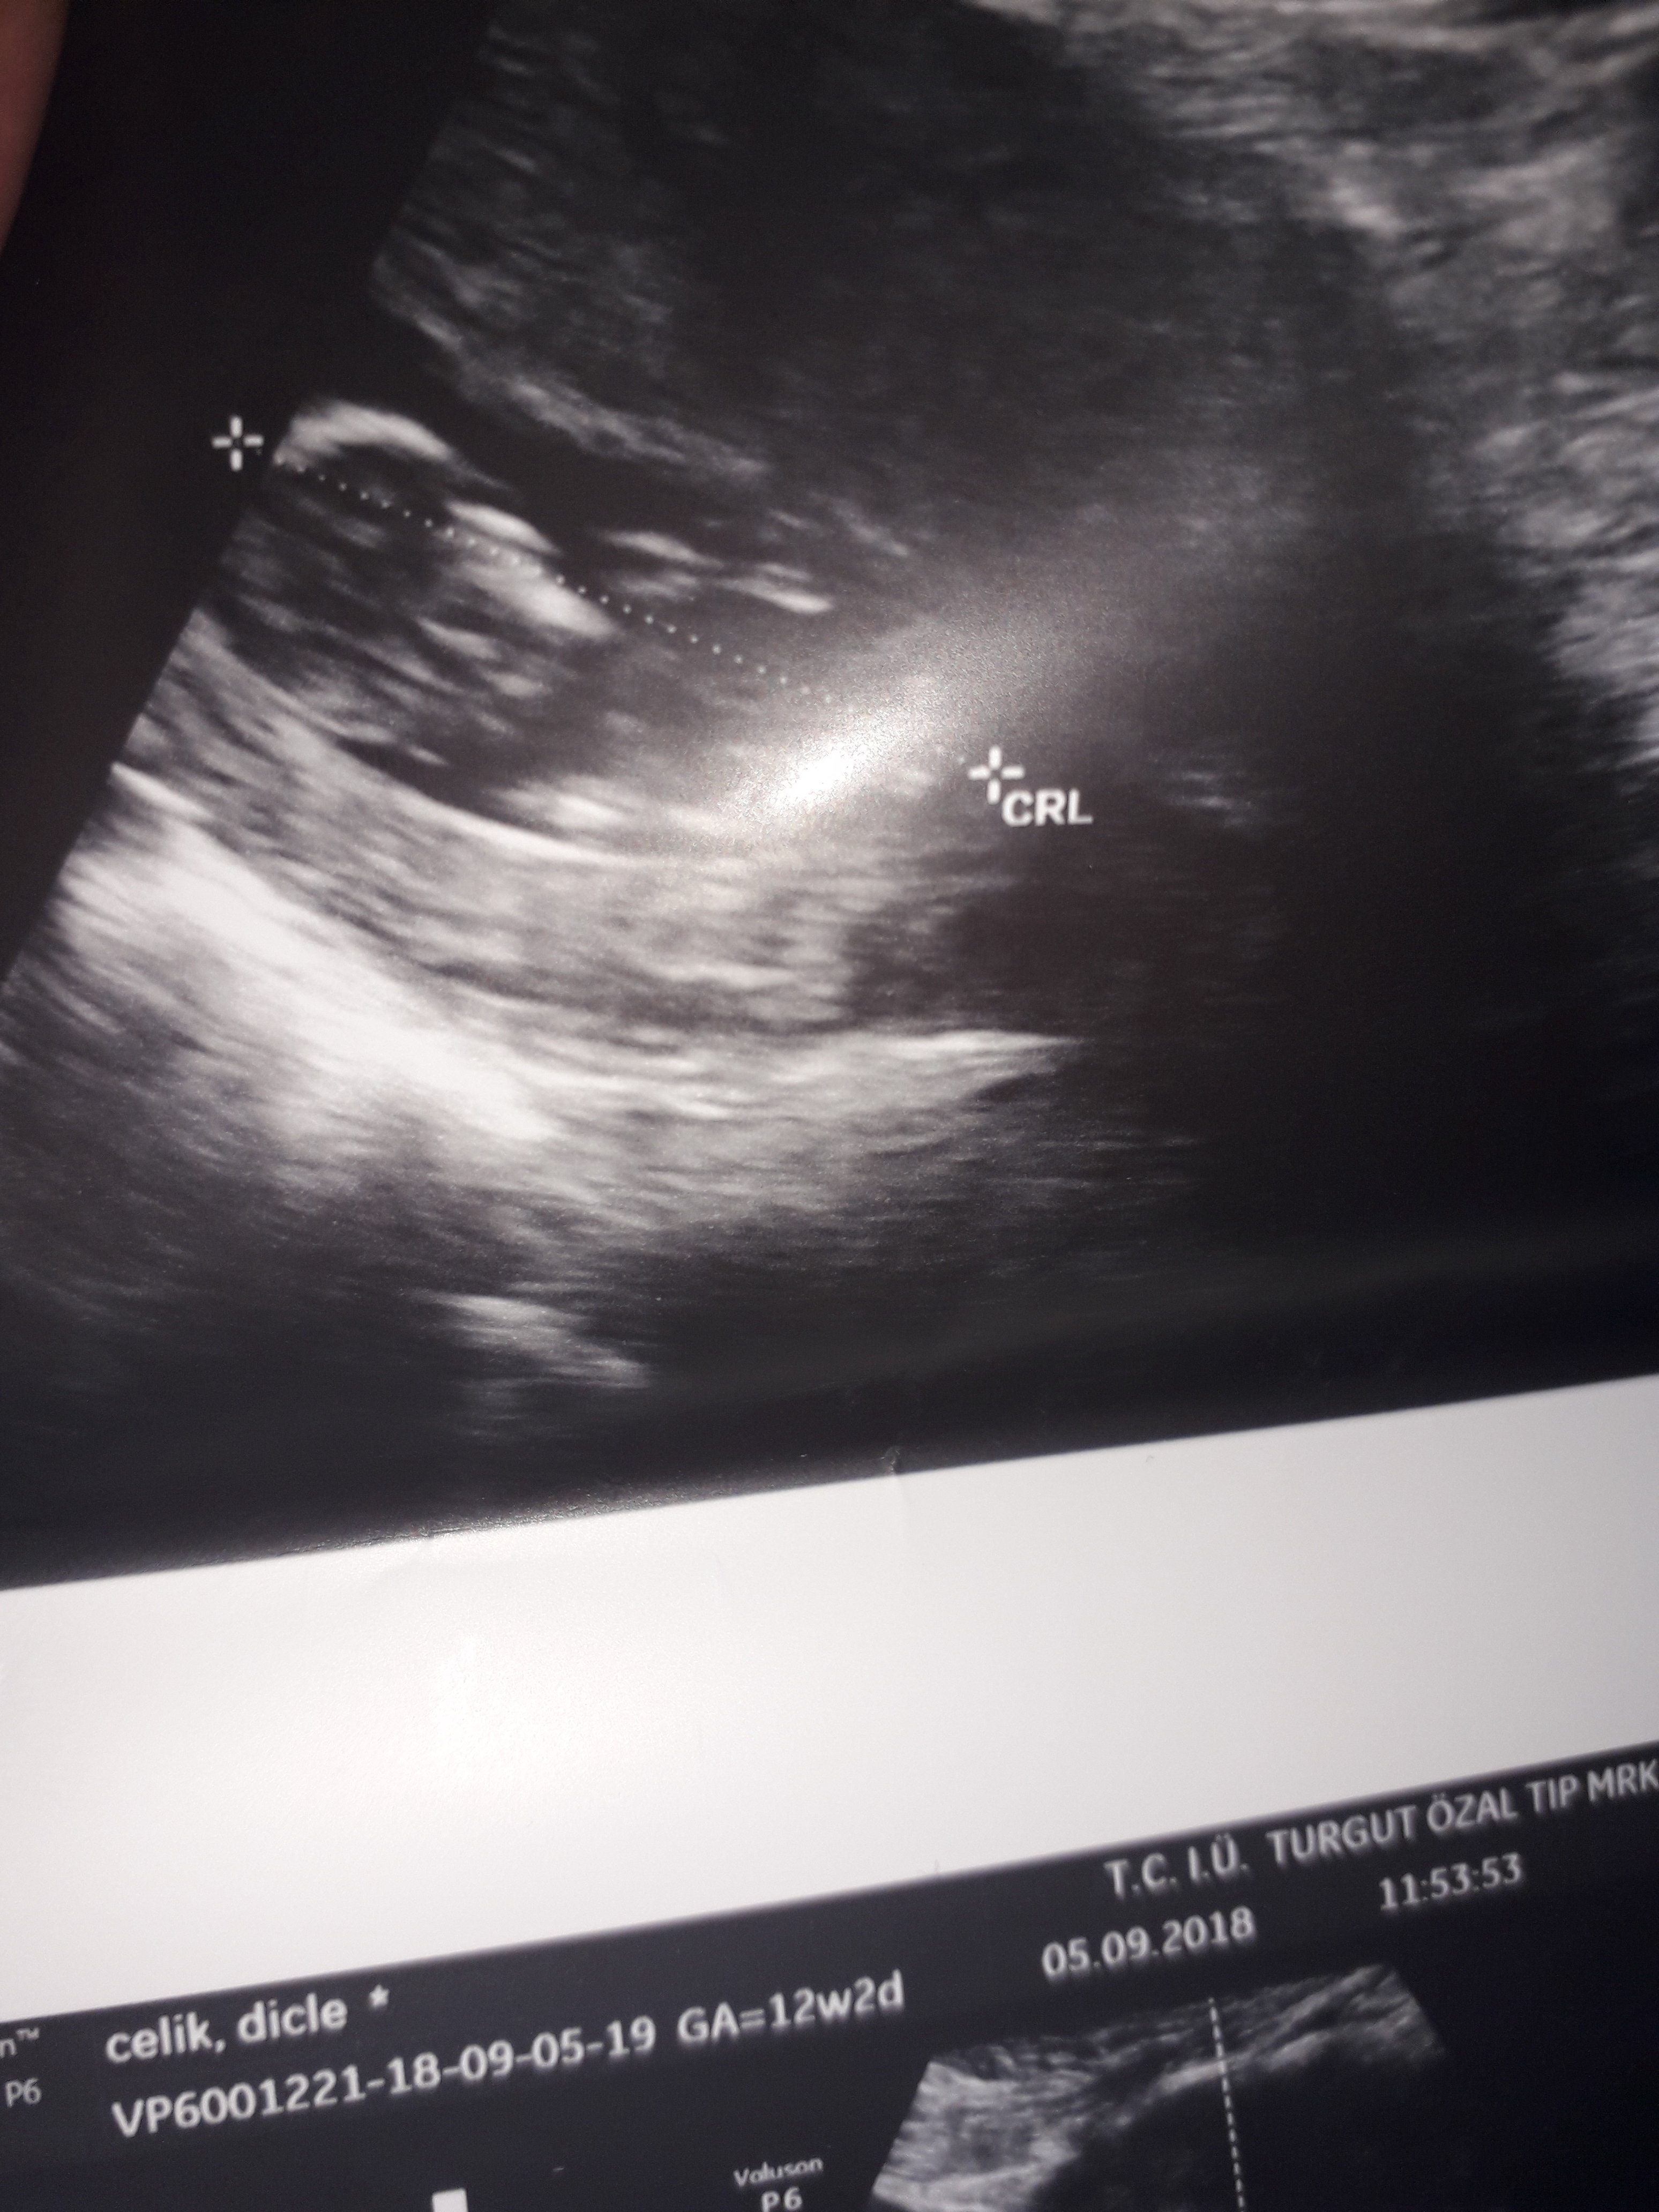

Dun malatyada verildi 12 +4 gunluk lutfen yorumlayin

nub çıkıntısının üzerinde imleç var cinsiyet anlaşılmıyor ilk sayfayı incelemenizi öneriyorum görselin kalitesi konu içinde yer alan görselle aynı olmalıdır.

Görsellerde nub çıkıntısı belli değil . Ultrasonu yapan doktor cinsiyeti hakkında bilgi vermiştir mutlaka ama şunu belirtmeden geçmeyeyim. Bu haftalarda cinsiyet tahmininde yanılma payı çok yüksek 17-19 ve 20 ci haftalarda bebeğin cinsiyetini net olarak öğrenebilirsiniz.